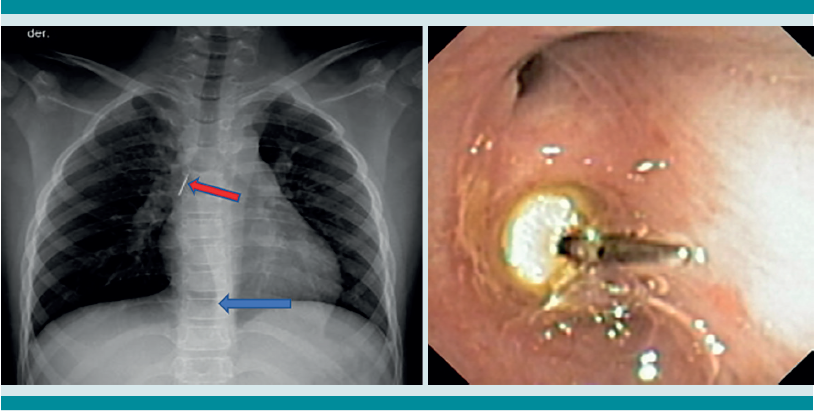

La radiografía de tórax es el primer estudio en un paciente pediátrico que llega al servicio de urgencias con sospecha de aspiración de cuerpo extraño. Gran parte de los objetos aspirados son radiolúcidos (biológicos y plásticos) y, por lo tanto, no se ven por este medio. Solo se logrará observar el cuerpo extraño en 15% de los casos (metálicos y huesos).1,6,8 Es más común identificar datos indirectos (aparecen hasta en 50% de las radiografías), que son consecuencia de la obstrucción en la vía aérea (atrapamiento de aire, atelectasias, consolidación, neumotórax) (Figuras 1,2,3,4,5). Respecto de las radiografías de tórax es que, incluso 45% pueden interpretarse normales, lo que puede resultar en un diagnóstico erróneo.1,6,9

La broncoscopia rígida ha sido el método de elección para la extracción de cuerpos extraños alojados en la tráquea o los bronquios principales. Su amplio canal de trabajo permite la ventilación del paciente durante el procedimiento, con una visualización adecuada e instrumentación accesible.2,11 En los últimos años y con el advenimiento de mejores instrumentos, la broncoscopia flexible ha ganado terreno no sólo en el diagnóstico, sino también en el tratamiento de la aspiración de un cuerpo extraño. La posibilidad de llegar a segmentos más distales dentro del árbol traqueo-bronquial, la mayor facilidad para maniobrar dentro de éste, así como la menor cantidad de lesiones en la mucosa que causa el equipo flexible son algunas de las ventajas que han llevado a varios grupos a preferir este procedimiento en lugar del rígido.11,12

Si al momento de consultar el paciente se encuentra en la etapa aguda, pero está estable, es decir, sin datos clínicos de inestabilidad cardiorrespiratoria, o se encuentra en la etapa oligosintomática pueden solicitarse los estudios de imagen. La radiografía de tórax es el principal recurso con el que cuentan la mayor parte de los servicios de urgencias. Es rápido, fácil, poco costoso y no requiere sedación. En caso de que sea un objeto radio-opaco, aportará el diagnóstico de manera rápida, y dará la localización del objeto (Figura 7). En caso de ser radiolúcido, la radiografía puede ser normal o mostrar los datos indirectos de obstrucción comentados. La tomografía axial computada de tórax puede considerarse si se cuenta con el recurso, tomando en cuenta lo mencionado.